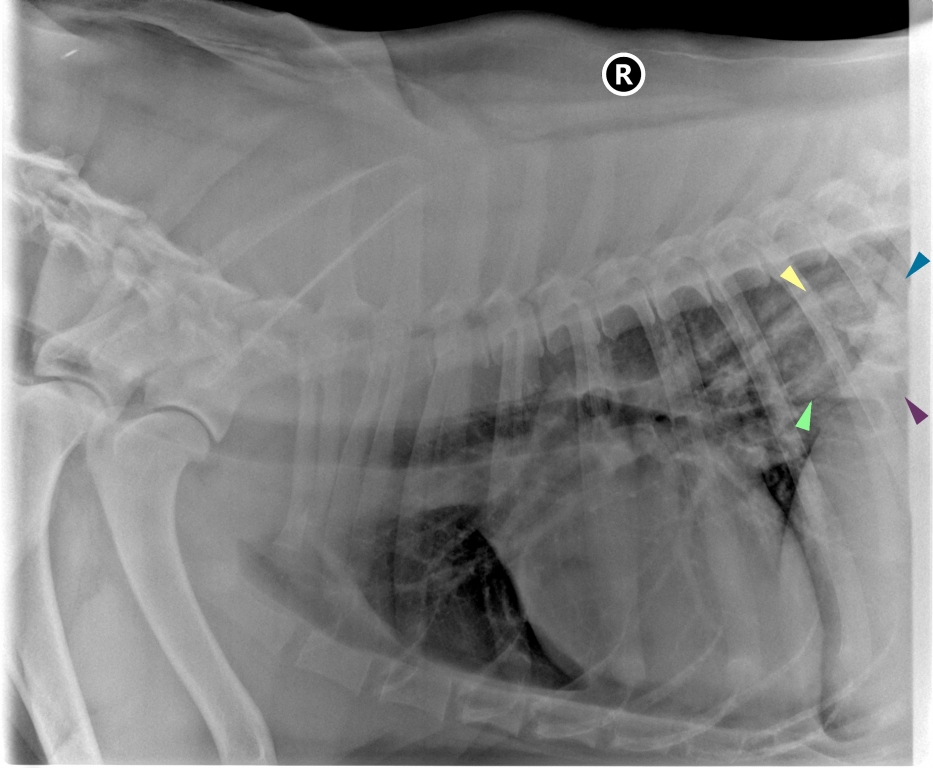

Jacey, a three-year-old Bernese Mountain Dog, was admitted to London Vet Specialists, in Belsize Park, North London, with a piece of bone stuck in her throat.

“The main areas this usually happens are just behind the voice box; where the oesophagus enters the chest; at the base of the heart and between the heart base and the diaphragm.

“She was given pain relief then anaesthetised to enable me to pass an endoscope down her throat and extract the piece of bone using a very large pair of forceps.

“Jacey’s oesophagus was then assessed for any signs of damage. We found she had developed a degree of inflammation and some mild erosions were noted, but she’d luckily escaped any significant injury.”